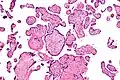

VUE can be of 2 types, low grade chronic villitis or high grade chronic villitis. Low grade chronic villitis involves less than 10 villi containing lymphocytes. Low grade chronic villitis can be either focal or multifocal. Focal has involved villi on only one glass slide, while multifocal has involved villi on at least two slides. High grade chronic villitis has more than 10 inflamed villi per focus. High grade chronic villitis is differentiated into diffuse and patchy. The term patchy is used if less than 30% of distal villi are involved. The term diffuse is used if more than 30% of distal villi are involved.

VUE has 2 prominent distinct patterns. Approximately 50% of the cases only involve the distal villi (mature intermediate and terminal villi) and do not involve the proximal stem villi, the anchoring villi embedded in the basal plate, and the chorionic plate. The second most common pattern (roughly 30% of VUE cases) involves the proximal stem villi (and possibly the chorionic plate) and the distal villi usually. This type of VUE is linked with foetal vascular obtrusive lesions (Obliterative Foetal Vasculopathy).[1][16]

Intermed. mag.